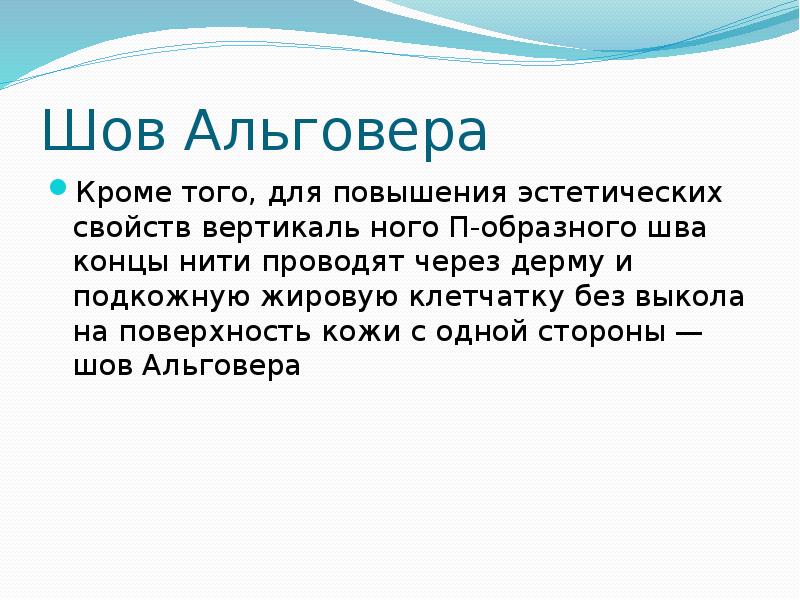

- 34. Шов Альговера Кроме того, для повышения эстетических свойств вертикаль ного П-образного